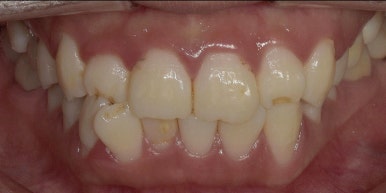

12전치 라미네이트, 크라운 치료 전후 비교

(전) 2023-06-23 (후) 2023-07-05

특히 오른쪽 아래 #42 치아는 기울어져 있던 치아가 반듯하게 개선되어 훨씬 고르게 변했고,

주변 치아와 조화가 잘 이루어지는 모습입니다.

라미네이트 치료 전후 상악, 하악 모습

(치료 전) 2023-06-23

(치료 후) 2023-07-05